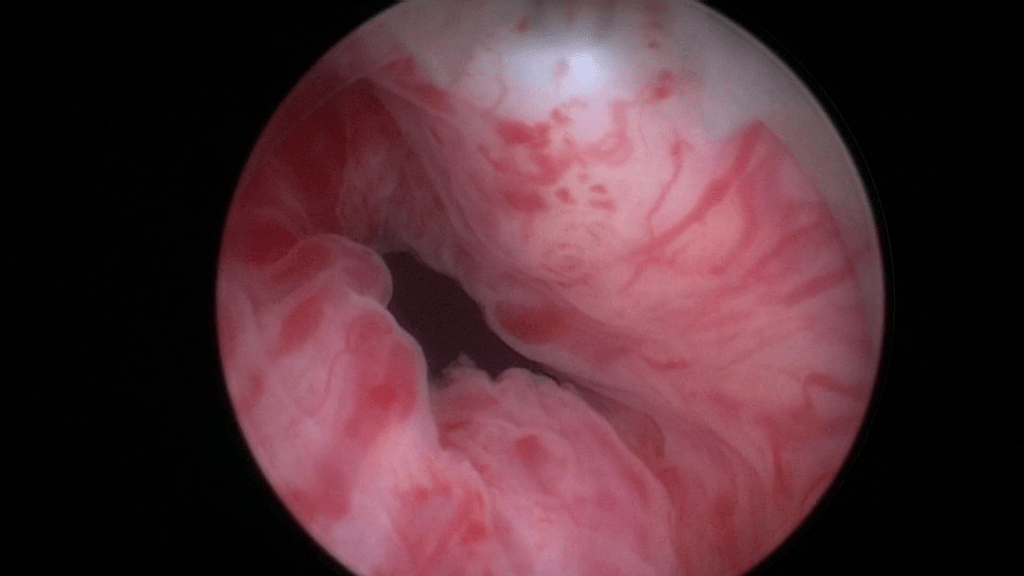

Documentation of the right ureteral orifice.

Documentation of the left ureteral orifice.